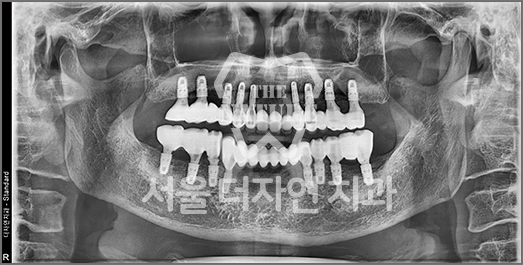

Full-Mouth Implant Restoration

Implant treatment for comprehensive full-arch restoration

This implant option is chosen to fully restore dental function. When missing teeth have been left untreated for an extended period,

the alveolar bone volume in both the maxilla and mandible is often insufficient. Therefore, a precise surgical plan must be established

with careful consideration of each patient's overall health condition.

• BEFORE: 2022.12.15

• AFTER: 2023.02.23